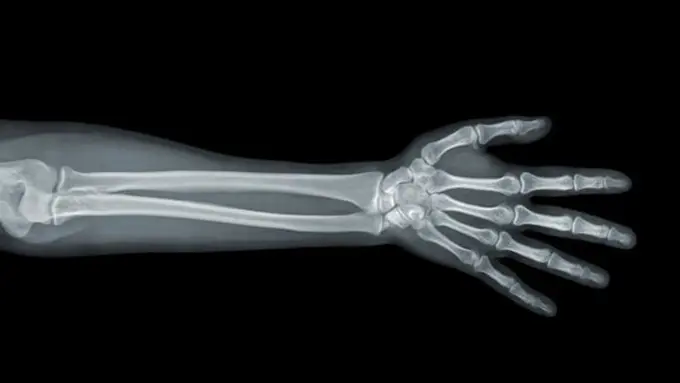

Berbicara tentang kalsium tentu tak lepas kaitannya dengan tulang. Kalsium memiliki peran yang baik dalam menjaga kesehatan tulang, terutama untuk mempertahankan kepadatannya dan menghindarkannya dari pengeroposan. Seiring dengan pertumbuhan badan, tulang juga akan ikut berkembang. Bila tidak ditopang dengan kebutuhan nutrisi yang cukup, seperti kalsium, maka bisa menyebabkan tulang menjadi rapuh dan berisiko mengalami osteoporosis di kemudian hari.

Menurut National Institute of Health, dalam jangka pendek, gejala kekurangan kalsium memang tidak begitu tampak. Hal ini dikarenakan tubuh mempertahankan kadar kalsium dalam darah dengan cara mengambil cadangan kalsium dari tulang. Akibat pengambilan cadangan kalsium pada tulang dalam kurun waktu yang cukup lama, sementara tubuh jarang menerima asupan kalsium yang cukup, tulang akan mengalami gangguan kesehatan secara bertahap.

Dalam jangka panjang, National Institute of Health, menjabarkan imbas minimnya asupan kalsium dalam tubuh, bakal memberikan dampak pengurangan massa tulang atau osteopenia hingga meningkatkanya risiko osteoporosis dan patah tulang. Sementara gejala kekurangan kalsium dalam jangka panjang menurut National Institute of Health, ditandai dengan munculnya mati rasa, kesemutan pada jari-jari kaki, hingga ritme detak jantung yang tak normal.